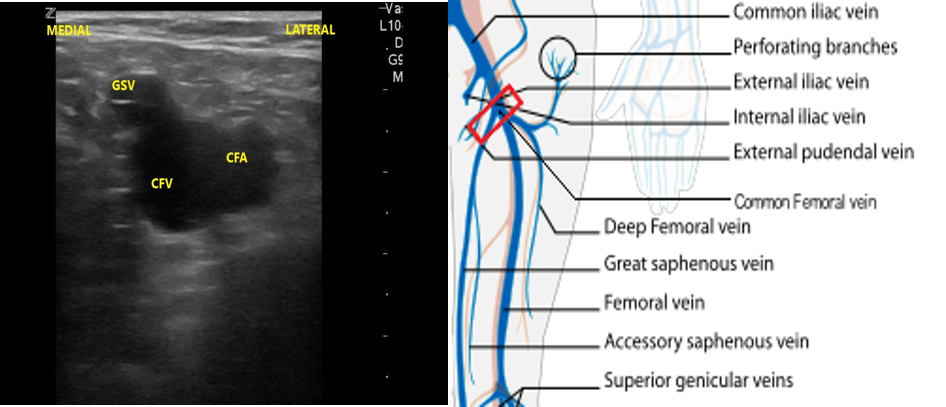

- The first venous confluence is the great saphenous vein (GSV) and common femoral vein (CFV). The GSV joins the CFV medially.

- The CFV forms a few centimeters distally to the GSV confluence, formed by the deep femoral vein (DFV) and femoral vein (FV). (The femoral vein is occasionally referred to as the superficial femoral vein, but as this structure is actually considered part of the deep venous circulation, it will be referred to as the femoral vein for the rest of this discussion.)

- Identify the inguinal crease at the very proximal medial thigh and place the transducer in a transverse orientation as indicated in Fig. 8. You should see the CFA and CFV as in the corresponding ultrasound image. If you see three vessels (CFA, CFV, SV), you are not proximal enough. Compress the CFV (Fig. 8 and 9).

- Slide the transducer distally 1 to 2 cm to the junction of the CFV and GSV ( 10 and 11) and compress.

- Figure 10. Junction of the CFV and GSV 1-2 cm below the inguinal canal with transducer orientation indicated (red rectangle).

- Figure 11. Compression of the CFV at the junction of the GSV 1-2 cm below the inguinal crease.

- Slide the transducer another 1 to 2 cm (3-4 cm distal to the inguinal ligament) to the junction of the DFV and FV. You will also see the CFA branch into the FA and DFA (Fig. 12). This constitutes completion of evaluation of “region 1.”